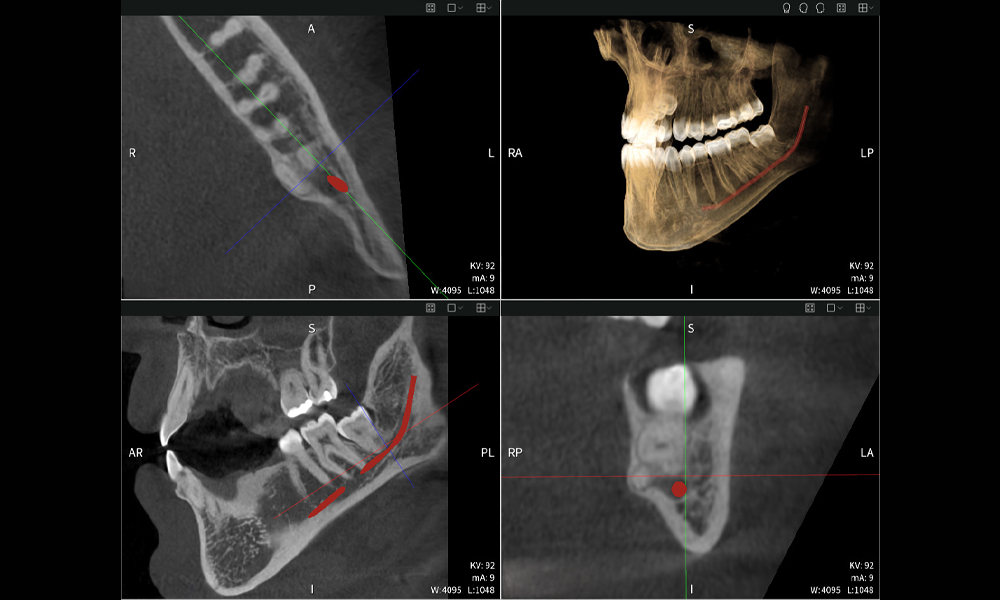

Below you will find a case from Dr. med. dent. Oliver A. Centrella, in which the CBCT images obtained with Seethrough Max provided crucial information on the complex anatomy and the critical relationship between the wisdom teeth and the inferior alveolar nerve. In this case, there is a indication for the surgical removal of the wisdom teeth.

• Top left: Axial cross-section of the left mandible (region 38) showing the inferior alveolar nerve (red) in proximity to the roots of tooth 38.

• Top right: 3D reconstruction of the entire mandible for orientation. The red-marked inferior alveolar nerve illustrates its location within the jawbone.

• Bottom left: Sagittal view of the mandible (region 38), highlighting the close spatial relationship between the roots and the nerve canal.

• Bottom right: Coronal view of the mandible (region 38), which is crucial for assessing the spatial position of the roots relative to the nerve.

Figure e: The panoramic X-ray serves as an initial assessment tool, showing the general positioning of the teeth as well as any potential pathological changes. Notably, on the right side (tooth 48), the situation following a crown amputation performed by an external practitioner is visible. The two severely curved roots remain in close topographical proximity to the inferior alveolar nerve within the bone. This suggests a deliberate decision to avoid the increased risk of nerve injury during a complete extraction, and represents a clinically relevant finding. In summary, CBCT scans with Seethrough Max, provide crucial information about the complex anatomy and the critical relationship between the wisdom teeth and the inferior alveolar nerve. This detailed preoperative diagnostic imaging is essential for safe and successful surgical procedures in the mandibular region.